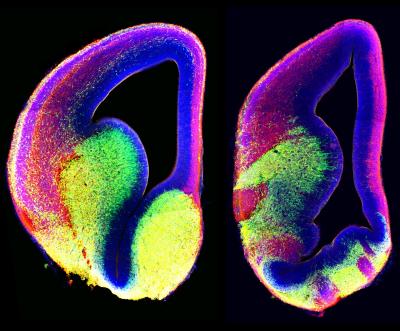

CHAPEL HILL, N.C. – As the brain develops, each neuron must find its way to precisely the right spot to weave the intricate network of links the brain needs to function. Like the wiring in a computer, a few misplaced connections can throw off functioning for an entire segment of the brain.

A new study by researchers at the University of North Carolina School of Medicine reveals how some nerve cells, called interneurons, navigate during the development of the cerebral cortex. Mutations in a key gene behind this navigation system underlie a rare neurological disorder called Joubert syndrome; a condition linked with autism spectrum disorders and brain structure malformations.

To do that, the UNC researchers and their collaborator, Dr. Tamara Caspary, at Emory University tracked brain development in mice with and without a gene called Arl13b. They found that the gene, when functioning normally, allows interneurons to use an appendage called the primary cilium as a sensor.

Neurons in mice without the Arl13b gene or expressing mutant Arl13b found in Joubert syndrome patients essentially had a broken antenna, causing the cells to get lost on the way to their destinations.